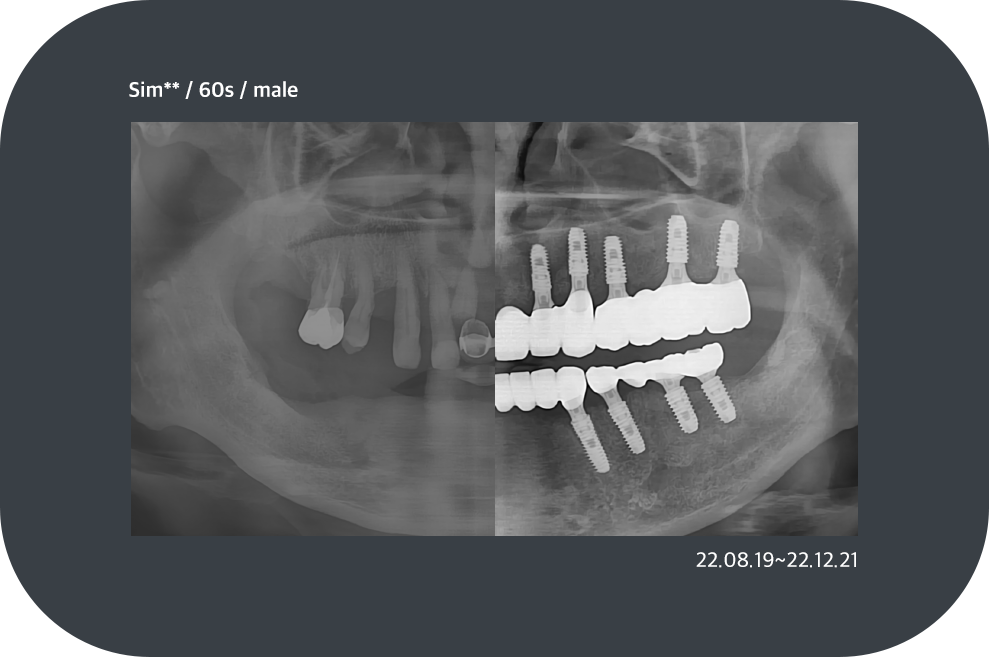

치료사례

임플란트 치료사례

*모든 증례 사진은 의료법 제23조, 제56조에 의거하여, 당사자의 동의하에 게시하였습니다.

*치료 사진은 모두 본원에서 치료한 환자분의 사진입니다.

*치료 사진은 모두 동일인의 사진이며, 동일조건에서 촬영하였습니다.

*개인의 차이에 따라 시술 및 수술 후 부작용이 발생할 수 있으며, 의료진과 충분한 상담을 받으시기 바랍니다.